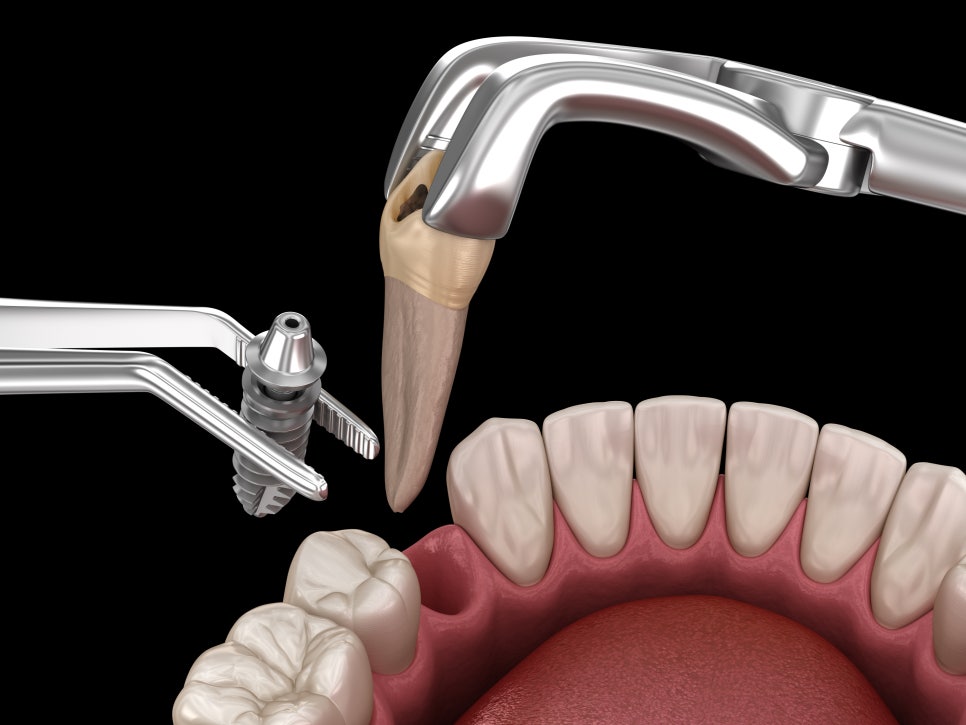

원데이 임플란트는 발치 즉시 임플란트를 식립합니다

하지만 원데이 임플란트는

'발치-식립-임시 보철 장착'을

단 하루 만에 진행하는

고난도 술식입니다.

- 발치 및 식립 (D-Day)

문제 치아를 발치함과 동시에

사전에 설계된 위치에

임플란트를 바로 식립합니다.